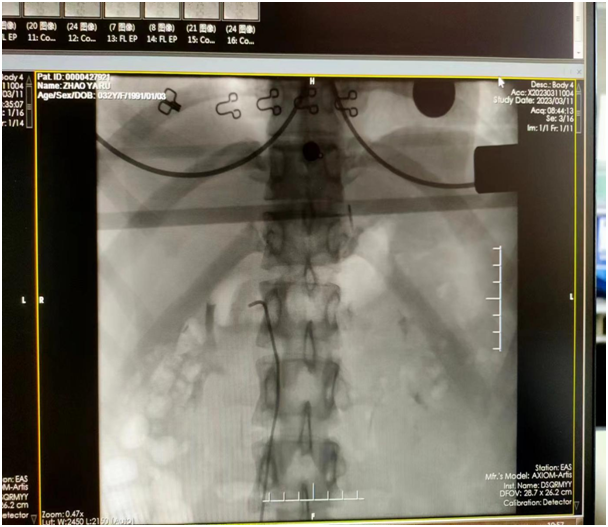

對照指南切點值顯示:卡托普利試驗后醛固酮下降率<30%,且醛固酮大于11ng/dl;輸注生理鹽水后醛固酮>10ng/dl,診斷為原醛癥。原發(fā)性醛固酮增多癥易造成難治性高血壓、心腦血管事件、腎損傷等嚴重并發(fā)癥,遠遠超過原發(fā)性高血壓引起的相關風險【1】。依據不同的臨床亞型采取手術或藥物保守治療的方式。腎上靜脈采血(AVS)是運用導管穿刺靜脈選擇性插入腎上腺靜脈后采集血樣,檢測某些指標判斷生理、病理學改變的一種介入檢查方法,主要用于鑒別原發(fā)性醛固酮增多癥的病因。目前,中國原醛癥診療的專家共識和國外原醛癥的診療指南均推薦AVS作為原醛癥功能分型診斷的金標準?;颊叻显┌Y的生化診斷標準,CT顯示不典型單側腎上腺病變,且有手術意愿,于是杭麗瑋副院長與高血壓團隊決定采用腎上腺靜脈采血的方法進行分型。

實驗室結果回報取血成功,并準確判斷患者為雙側分泌優(yōu)勢型。雙側優(yōu)勢分泌一般建議采用藥物治療來改善癥狀,但是目前研究顯示手術可能為患者帶來更大的獲益。螺內酯(MRA)是一線用藥,可以有效地降低醛固酮水平,但該藥對醛固酮的拮抗是非選擇性的,有報道MRA的副作用發(fā)生率高達50%,如導致高血鉀、胃腸道反應、男性乳房發(fā)育及性功能減退、女性月經紊亂、乳腺刺痛及中樞神經癥狀等,因此年輕人可能不太愿意接受【2】。其次,研究顯示藥物治療與手術治療對于患者遠期預后來說,手術可降低中遠期心血管死亡率【3】。但是手術僅適用于醛固酮腺瘤、單側腎上腺皮質結節(jié)增生、醛固酮癌的患者,而不適用于雙側腎上腺增生(特醛癥)、單側醛固酮腺瘤伴有對側腎上腺增生、家族性醛固酮增多癥。對于不想接受藥物治療又不想行手術治療的患者,腎上腺動脈栓塞術是一種有效的替代治療方法。超選擇性腎上腺動脈栓塞術是通過導管將化學消融劑超選擇地注入腎上腺動脈,直接選擇性毀壞腎上腺組織,阻斷醛固酮產生的微創(chuàng)治療方法,與傳統手術切除或經腹腔鏡手術切除比較,具有微創(chuàng)、并發(fā)癥發(fā)生率低、住院時間短、費用低的優(yōu)勢【4-5】。其三有研究顯示無水乙醇隨血流分布對彌漫生長的分泌醛固酮的微結節(jié)或細胞簇進行損毀,相當于腎上腺部分切除,術后沒有出現腎上腺皮質激素水平降低,也無腎上腺皮質功能減退現象【6】。杭麗瑋教授綜合考量,通過與家屬充分溝通,擬對左側腎上腺采用超選擇性腎上腺動脈栓塞術。